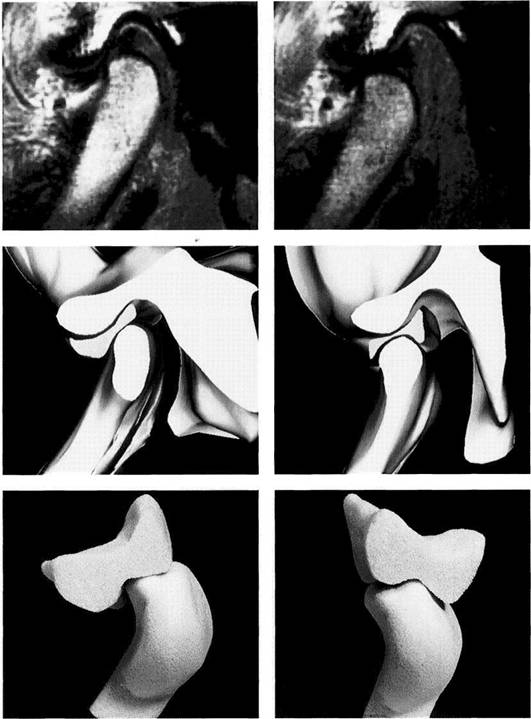

Three Dimensional Images of the Temporomandibular Joint...

Advances in computer technology have made it possible to create three-dimensional images from single axial or sagit­tal slices (Ray et al. 1993, Rodgers et al. 1993). This has helped to further improve the ability to make an accurate diagnosis and to more effectively plan treatment prior to surgery (Alder et al. 1995). Measurements on the computer screen can be used with confidence because these values agree with the anatomical measurements (Raustia and Phytinen 1990). The computed spatial objects can be rotated and viewed on the monitor from any direction. With the right software it is also possible to separate the condyle

from the fossa. This permits accurate inspection of the medial part of the joint. For better visualization, structures that are of distinctly different shades of gray (measured in Hounsfield units) can even be displayed in different colors.

Three-dimensional imaging of the temporomandibular joint is especially indicated for ankylosis and tumors where it helps the surgeon plan exactly how much tissue to remove. Hyperplasia of the coronoid process is another classic pre­operative indication (Honig et al. 1994).

Three-dimensional repre­sentation of a temporo­mandibular joint

A three-dimensional image of the joint can be reconstructed from CT measurement data. Further detail can be seen by separating the condyle from the fossa. Special software (Denta-CT) is available for the orofacial region and is designed especially for three-dimensional imaging of the alveolar processes (Abrahams and Kalyanpur 1995).

Three-dimensional representation of the fossa

An inferior view of the articular fossa from Figure 399 is shown. This view permits scrutiny of the condylar path and the articular em­inence. The image can be rotated on the monitor so that the mor­phology and inclination of the joint pathway can be calculated. This de­termination has no clinical rele­vance, however. In edentulous pa­tients the fossa lies more anterior than it does in patients with teeth. Its sagittal position depends on how long the patient has been edentulous (Raustia et al. 1998).

Three-dimensional repre­sentation of the condyle

This separate image of the condyle allows inspection of the joint surface. This type of image is only important for primary temporo­mandibular joint diseases, how­ever. Changes in the articular sur­faces due to dysfunction can be adequately diagnosed clinically and do not require three-dimensional imaging, as the radiographic find­ings would not change the treat­ment.